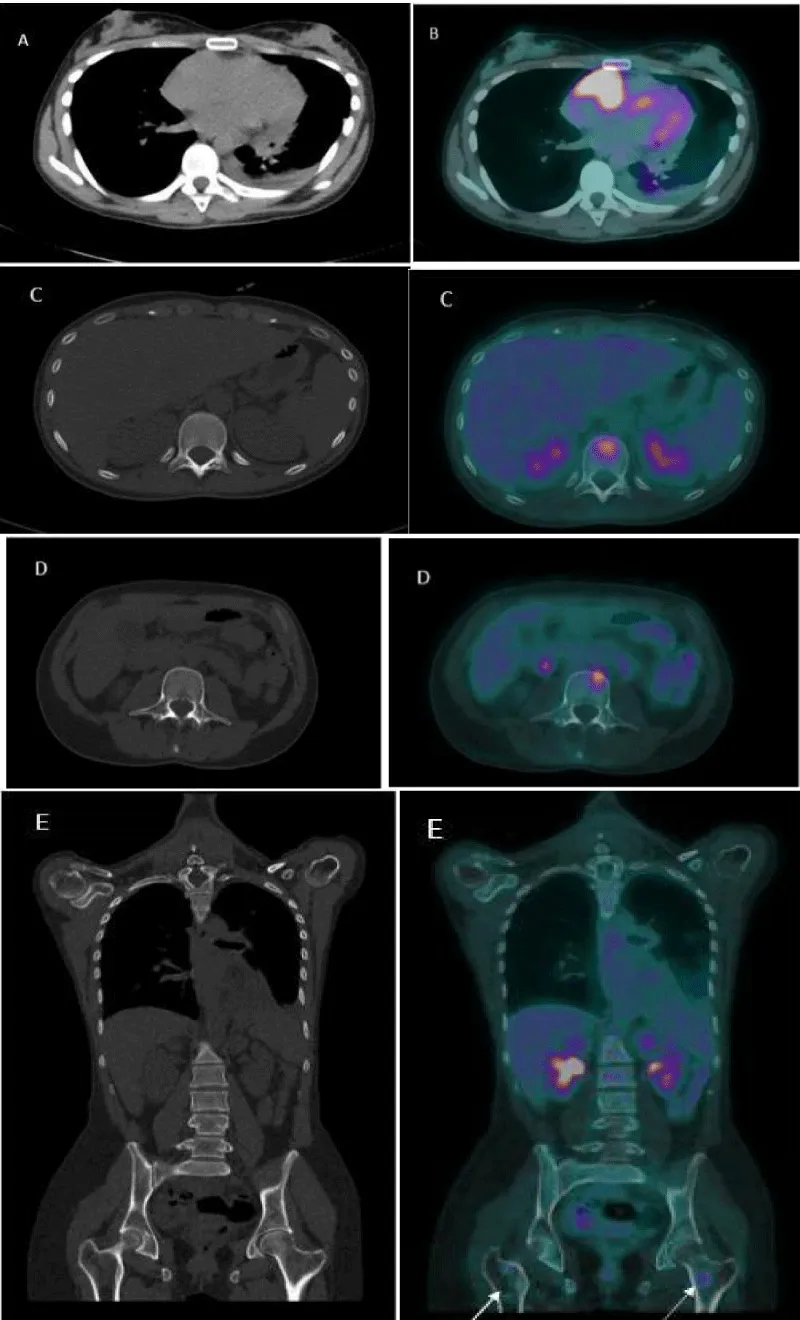

To better delineate and characterize the cardiac mass, a chest CT was performed (Figure 1). This examination revealed moderate pericardial effusion with the existence of a low attenuation mass in the right atrium, extending along the pericardium with heterogeneous enhancement, of approximately 3.5 cm, which corresponds to a cardiac tumor. Cardiac magnetic resonance imaging (Figure 2) exposed a cardiac mass at the level of the right atrium with extension into the pericardium and free wall of the right ventricle and heterogeneous late enhancement, being hypointense on T1 and T2, This is not the most typical pattern, which usually consists of low signal T1-weighted sequences, and increased signal and central areas of hyperintensity on T2weighted, consistent with hemorrhage and necrosis, and areas of moderate signal intensity in more peripheral regions [3]. Because of their high vascularity, strong signal enhancement is seen after the administration of IV gadolinium [3]. However, given the propensity of angiosarcomas to necrosis and hemorrhage, these often have heterogeneous signals on cardiac MR images [3]. Fluorodeoxyglucose-18 combined with positron emission tomography/computed tomography (18F-FDG-PET/CT) (Figure 3) confirmed pathological metabolic activity in the recognized mass in the right atrium extending along the pericardium with intensely increased FDG uptake (SUVmax) of 17.3. Moderate Pericardial effusion was noted and multiple hypermetabolic foci in the bodies of the D12, L2, and L3 vertebrae, as well as in the proximal third of both femurs, without evidence of structural lesions on CT with SUVmax of 6.9.

Download Image

Figure 3: An 18F-FDG-PET/CT scan. A computed tomography (CT) and B fused PET/CT: Pathological metabolic activity in the known mass in the right atrium extending along the pericardium with intensely increased FDG uptake (SUVmax) of 17.3. Moderate Pericardial effusion was noted. C, D, E (CT and fused PET/TC) showed hypermetabolic foci in the bodies of the D12 and L3 vertebrae, as well as in the proximal third of both femurs (arrows), without evidence of structural lesions on CT with SUVmax of 6.9.